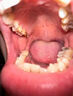

肠胃消化

> 胃热口臭

胃热口臭